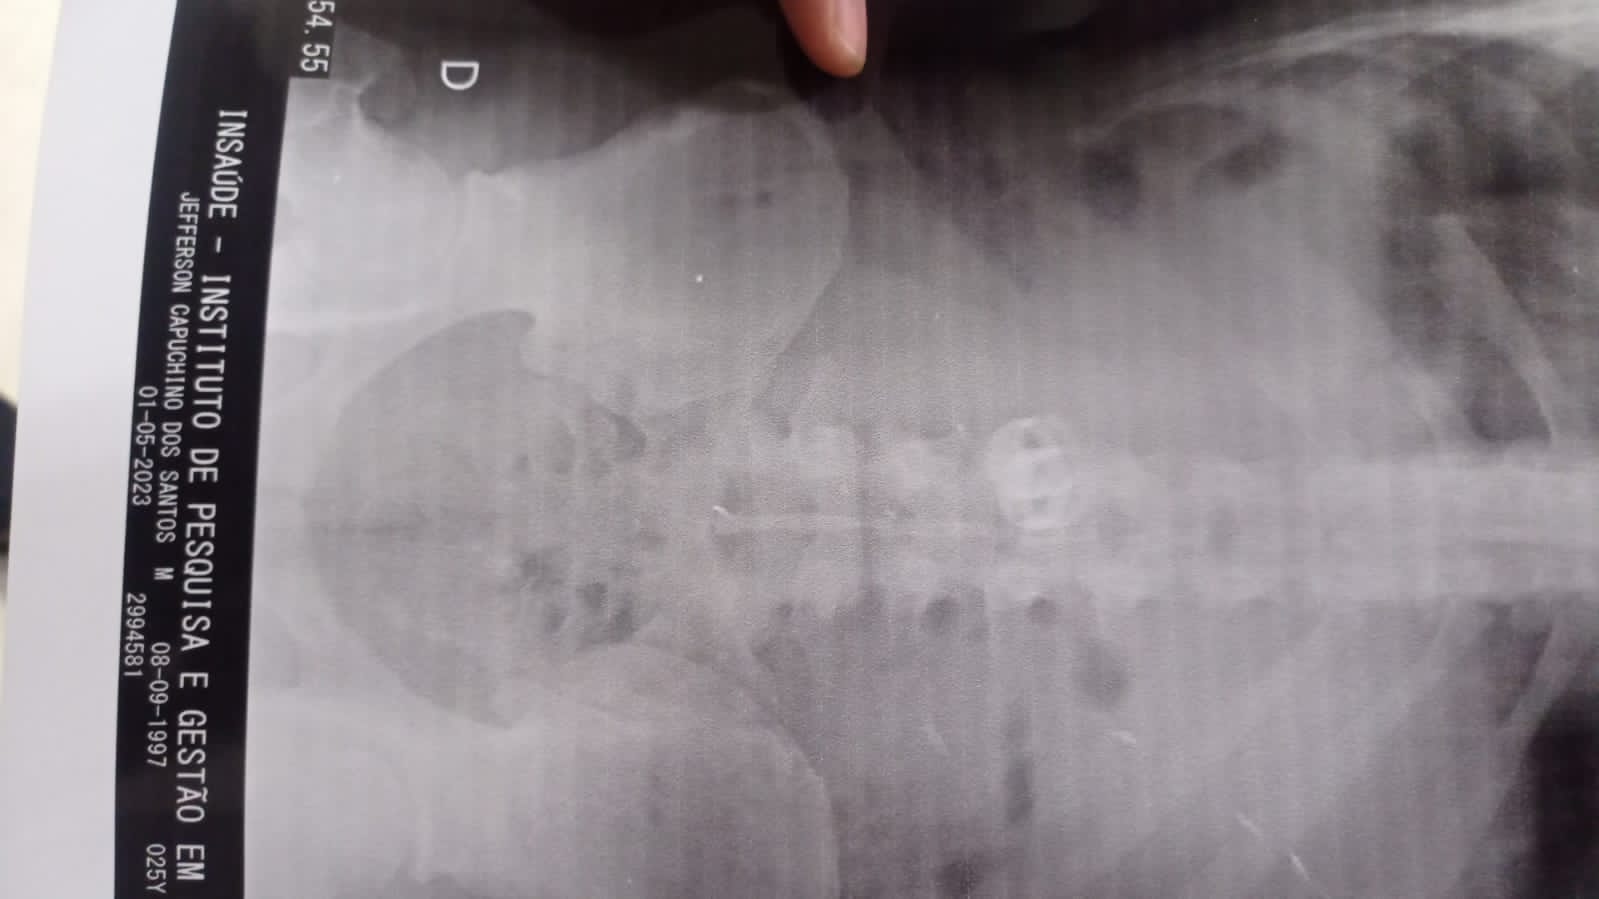

Os objetos foram detectados, após exame de raio – x, na Unidade de Pronto Atendimento (UPA) Central.

A dupla foi encaminhada para a UPA Central, devido às lesões ocorridas durante a perseguição, e porque um dos criminosos engoliu as alianças das vítimas, detectadas por radiografia do estômago.